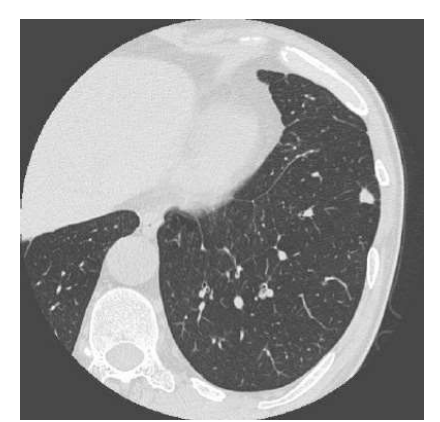

・solid nodule(充実結節)

・pure ground-glass nodule(pure GGN:いわゆるスリガラス影)

・part-solid nodule(狭義の部分充実結節)